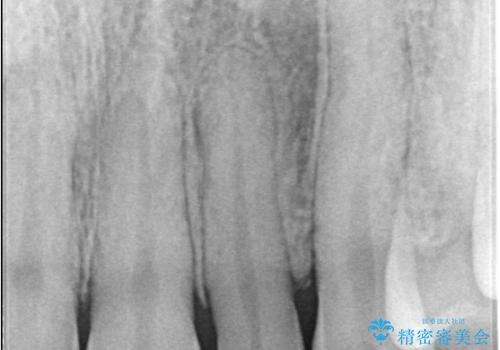

- 歯並びを矯正で整えたあと、上顎左右2番の歯(前歯の横の歯)の「矮小歯(歯が小さい状態)をオールセラミッククラウンで審美修復した症例です。

矯正によって歯並びはきれいに整いましたが、前歯全体のバランスをより自然で美しく仕上げるため、上顎左右2番にオールセラミッククラウンによる審美修復を行いました。

矮小歯はもともと歯が小さいため、削る量を最小限に抑えた負担の少ない治療が可能です。

また、自然な色合いや形になるよう、歯科技工士と連携し、写真を撮影しながら細かく色合わせを行い、周囲の歯になじむよう丁寧に仕上げています。